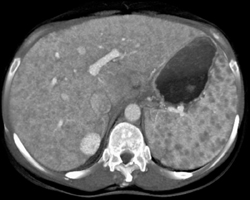

Sarcoidosis